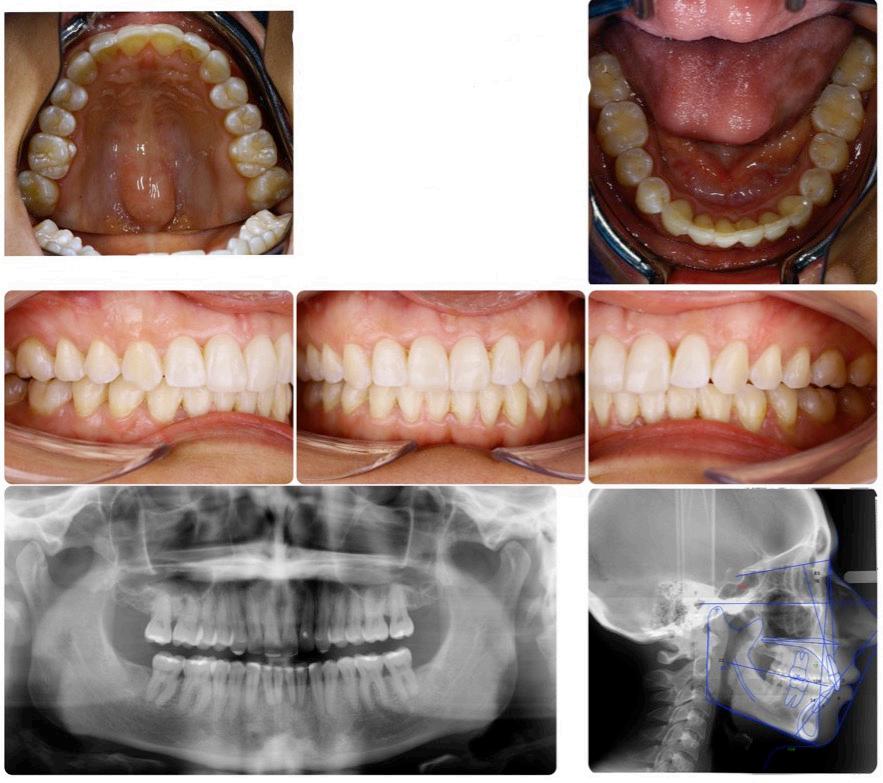

A 32-year-old female presented with facial asymmetry, with her chin shifted to the left, a retrognathic mandibular profile, a horizontal growth pattern, Class I molar and canine relationships on the right side, Class II molar and canine relationships on the left side, and upper and lower moderate anterior crowding.

Pre-treatment T-Scan 10 recordings were made to evaluate the pre-treatment occlusion using a standard T-Scan diagnostic protocol that involves five specific recordings (pre-treatment records, Figures 1-4).

presented with upper and lower moderate-to-severe crowding, along with molar Class III and canine Class I right side alignment, molar and canine Class II left side alignment, and mild anterior overbite. The lateral cephalometric tracing before treatment determined an ANB angle = 4.2 degrees, NL-NSL =10.0 degrees, and ML-NSL= 20.0 degrees, which corresponds to a skeletal Class II with clockwise maxillary base rotation, and a horizontal growth type.

Figure 1: Intraoral photographs, and panoramic and lateral cephalometric radiographs before treatment. The patient Figure 2: A Multi-bite recording before treatment illustrating an Anterior/Posterior Force % ratio (A/P ratio) = 8.3%/92.7%.

Figure 3: A right lateral excursion before TX: 0.82 sec with eventual canine guidance. The Blue Line extending from Point C to D indicates the prevalence of a working side group function guidance pattern that precedes the anterior disclusion at D. Throughout the excursion teeth #s 3 and 5 control the right working movement until eventually the anterior right quadrant controls the late excursion (when the red anterior quadrant line reaches 100% force at 2.8 seconds).

Figure 4: The left lateral excursion before Tx. Although the excursive recording ends with a DT = 0.96 sec., the DT is actually infinite, because the orange posterior left quadrant is never replaced by the anterior left quadrant. Guidance control is on teeth #s14 and 15 with working-side interferences, along with a non-working side interference on tooth #3.

The overall treatment time for this patient was 18 months using traditional straight-wire technique, Victory series brackets (3M Unitek, Monrovia, USA), 0.022 x 0.028’’ slot, and an MBT prescription (the bracket prescription provided dimensional positioning data for the orthodontic wire, being the torque, the angulation, and the offset).

A T-Scan 10 occlusal analysis was repeated after the orthodontic treatment to compare to the pretreatment condition (Table I) (post-treatment records, Figures 6-9).

Table 1: Pre and post-treatment T-Scan data indicating improvement in the OT and the left side-right side force % imbalance. However, the closure force outlier contacts within the OT remained similar (#s 3, 4, 15). Treatment shifted the first contact #3 to #2 (more distally). The Total Anterior Force % and the Ant/Post % ratio remain unchanged. The left and protrusive Disclusion Times were partially improved, while the right DT worsened.

Figure 5: Interproximal reduction with crown remodeling for papilla preservation. The bracket on the tooth #9 was intentionally rotated distally to improve the root angulation. Figure 6: The post treatment intraoral photographs, the panoramic radiograph, and the lateral cephalometric radiograph with tracing. An increased ANB angle resulted from changing lower incisor root position with counterclockwise mandibular rotation. The decreased ML-NSL angle resulted from leveling the occlusal plane. 4: The Tx.